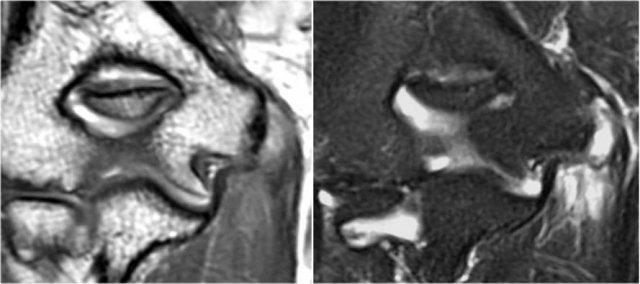

Osteochondral lesions

OC lesion of capitellum

Tổn thương sụn xương là tên gọi mới của bệnh viêm xương sụn bóc tách hay OCD.

Quá tải valgus mãn tính có thể gây ra tổn thương sụn xương ở phía ngoài của khuỷu tay.

Đây là kết quả của các lực va chạm và lực cắt lặp đi lặp lại.

Hình chụp X-quang của một vận động viên bóng chày 15 tuổi với tiền sử đau khuỷu tay 4 năm và gần đây có triệu chứng kẹt khớp.

Có một vùng thấu quang khu trú ở chỏm con và một số mảnh vỡ.

Đây là hình ảnh điển hình của tổn thương sụn xương chỏm con và hiện tượng kẹt khớp có thể là kết quả của các dị vật trong khớp.

MR-arthrogram xác nhận tổn thương sụn xương.

Có gadolinium nằm giữa xương cánh tay và tổn thương sụn xương, cho thấy tổn thương này không ổn định.

Nếu không có gadolinium, hãy tìm dịch khớp chui xuống dưới mảnh sụn xương.

Có một mảnh thể tự do trong ngách sau của khớp quay-cánh tay.

Notice also the fragmentation as seen on the axial image.